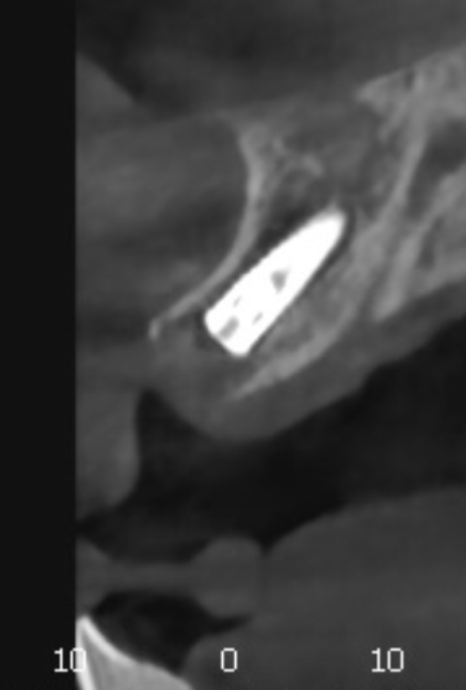

다행히 CT 분석 결과,

잇몸뼈의 폭과 길이가 충분하셔서

발치 당일 즉시 임플란트를

식립할 수 있었습니다.

240119